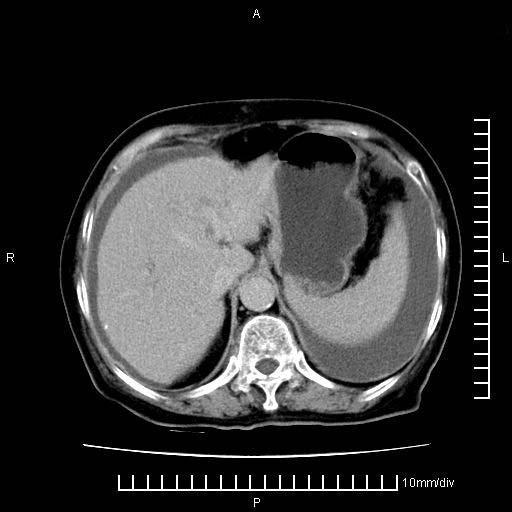

标题: CT28280:腹部增强:女性,80岁

上腹疼痛月余,外院核磁诊断胰腺癌。现临床示右下腹可明显触及包块,可片子上怎么没有看到?

1.胰腺颈体部癌。

2。腹腔积液。

3。右胸腔积液,伴右肺下叶部分萎陷。

4。右肾盂囊肿。

胰腺体部癌累及周围器官,腹膜、粘连

1。胰腺ca伴腹膜腔转移

2。肝左叶低密度灶,考虑转移可能

胰腺体部癌累及周围器官,腹膜、粘连,临床摸到的可能是粘的组织

支持胰腺癌肝内转移,腹水改变。

胰腺结构模糊,胰尾部见囊性包块,周围脂肪密度增高,左肾前筋膜增厚,胸水、腹水。不符合胰腺ca伴腹膜腔转移。考虑胰腺炎伴假性囊肿形成、胸腹腔积液。

1、考虑胰腺癌伴腹膜腔转移,胸腹水。

2、肝脏转移可能。

3、右肾盂囊肿。

1)考虑胰腺癌并胰腺假性囊肿形成。2)肝内低密度灶,不排除转移。3)右肾盂积水。4)腹水。5)右侧胸腔积液并右肺下叶部分膨胀不全。

考虑胰腺ca伴腹膜腔转移、肝左叶转移、右肾积水。右胸腔积液。